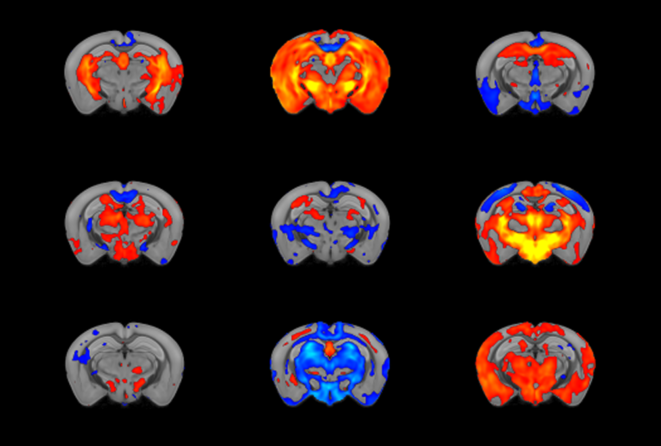

L'imagerie cérébrale - par exemple, l'IRMf - peut être utilisée pour décomposer de manière fiable la complexité de l'autisme en sous-types significatifs, en utilisant par exemple la souris.